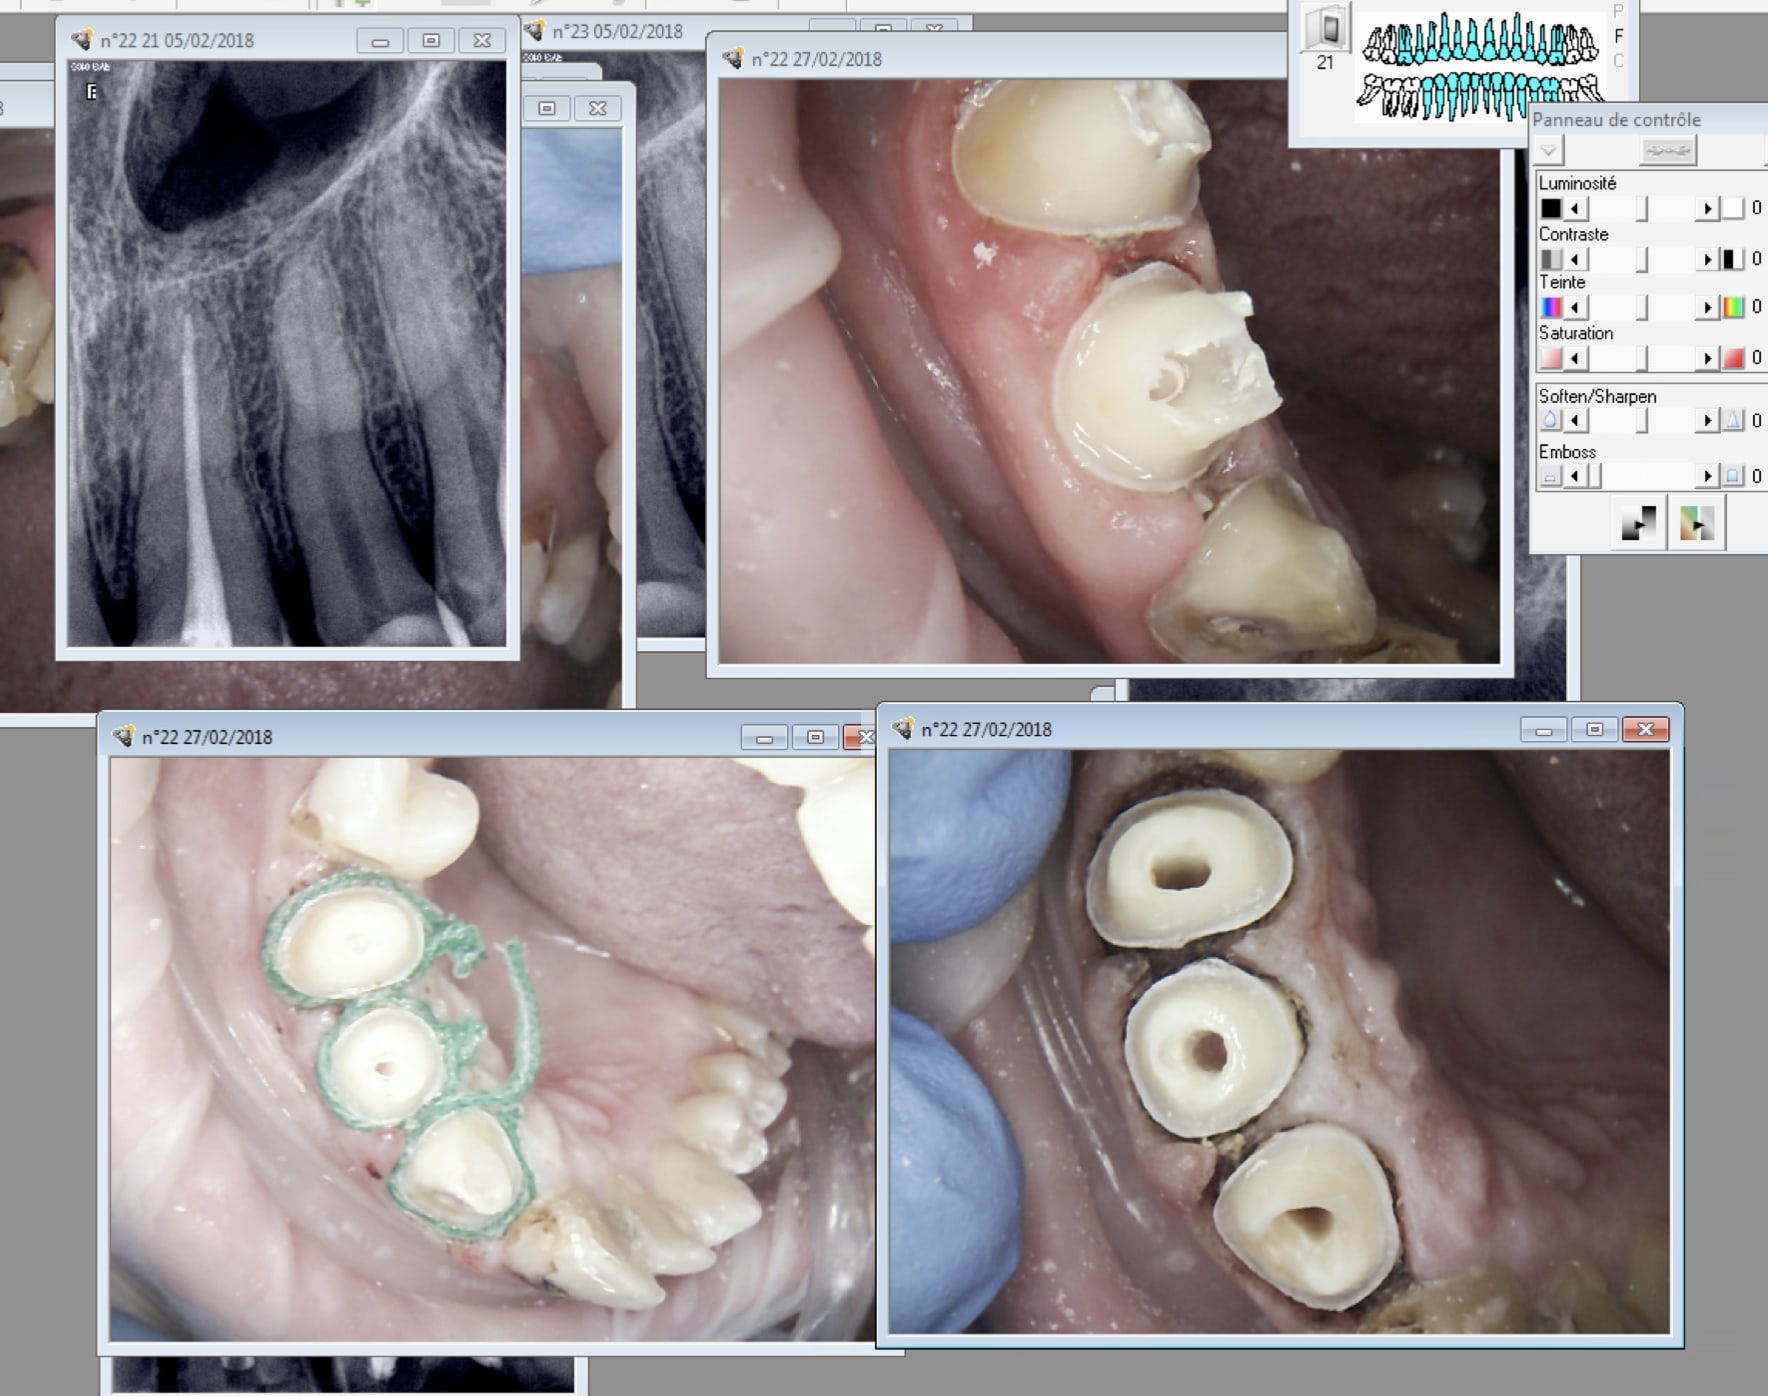

En cours : 1. endo 2. taille juxta. 3. fils.

Dépose du deuxième fil.

Empreinte.

Pivot anatomique. attention ca bouffe de l'image et te fait planter l'ordi.